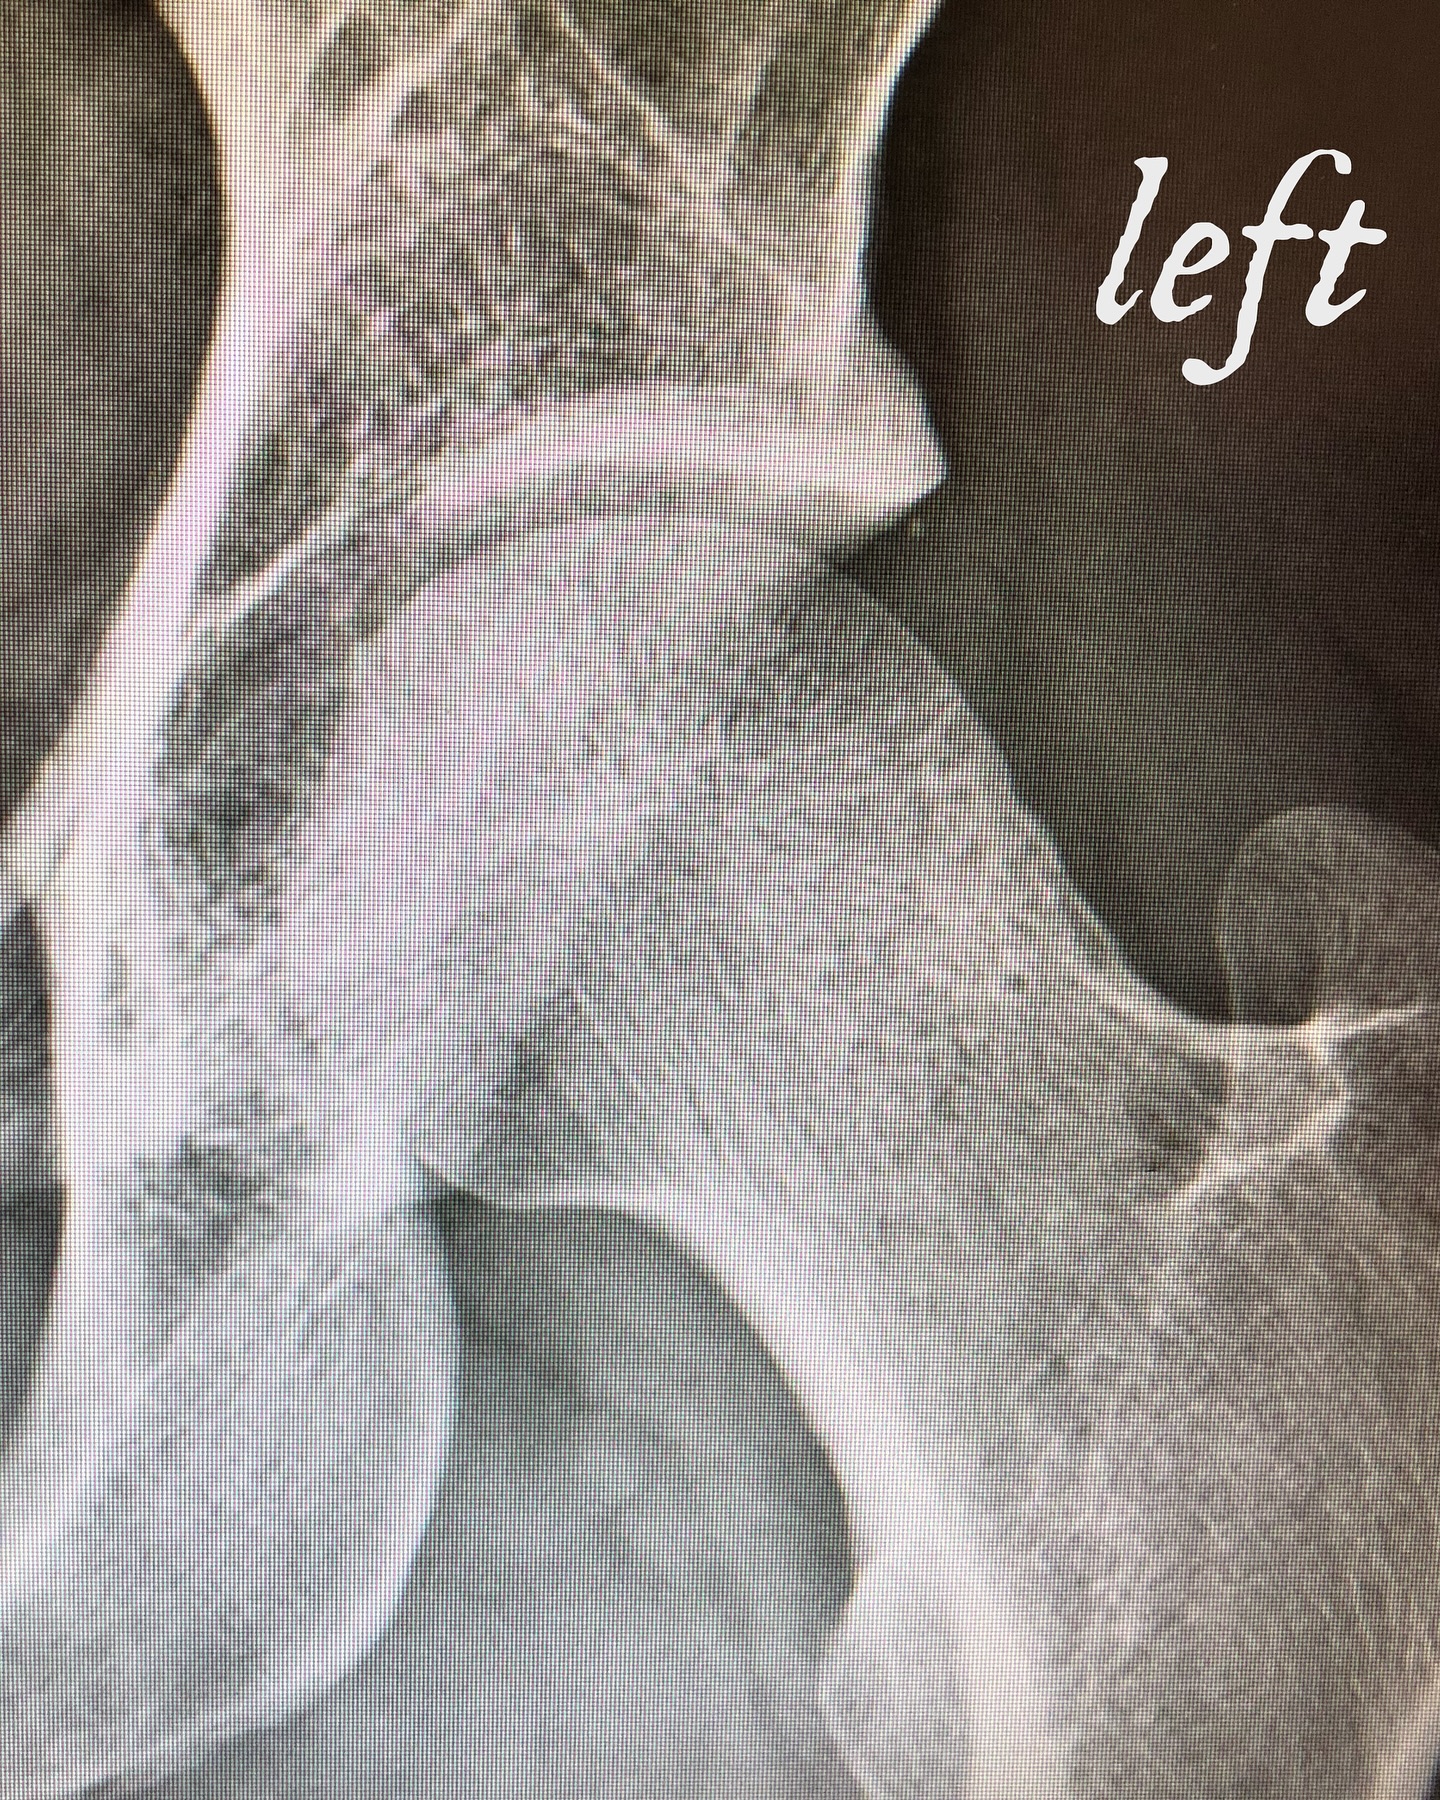

He continued, “Frustrated and in search of a solution, an MRI in October of 2020 indicated that I had suffered a ‘femoroacetabular impingement’ as the result of an abnormal bone growth on the neck of my left femur bashing up against my hip labrum when I’d go running. My doctor — who I’d known had helped many professional athletes with the same condition — recommended an arthroscopic procedure to correct the issue.”

In November 2023, Jay revealed his health struggles after announcing he left Slipknot for ‘creative’ reasons. He posted photos on Instagram showing himself with crutches and in the hospital, explaining his ongoing health plan.